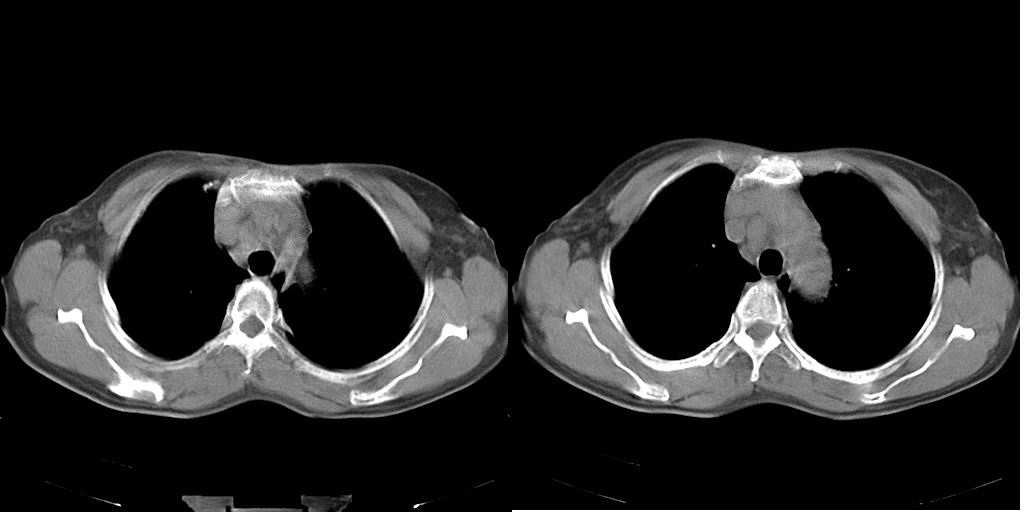

以下是引用dyqct在2007-1-23 15:01:00的发言:[br]左肺下叶实变、略萎陷,近肺门下部密度不均。上腔静脉后及隆突前淋巴结太多了,左下叶气管边窄、截断。余未见异常。[br]考虑:1、左肺下叶中心型肺癌伴肺不张、纵隔淋巴结转移;[br] 2、建议增强扫描并做任意平面重建确定肿块范围及支气管受累情况。